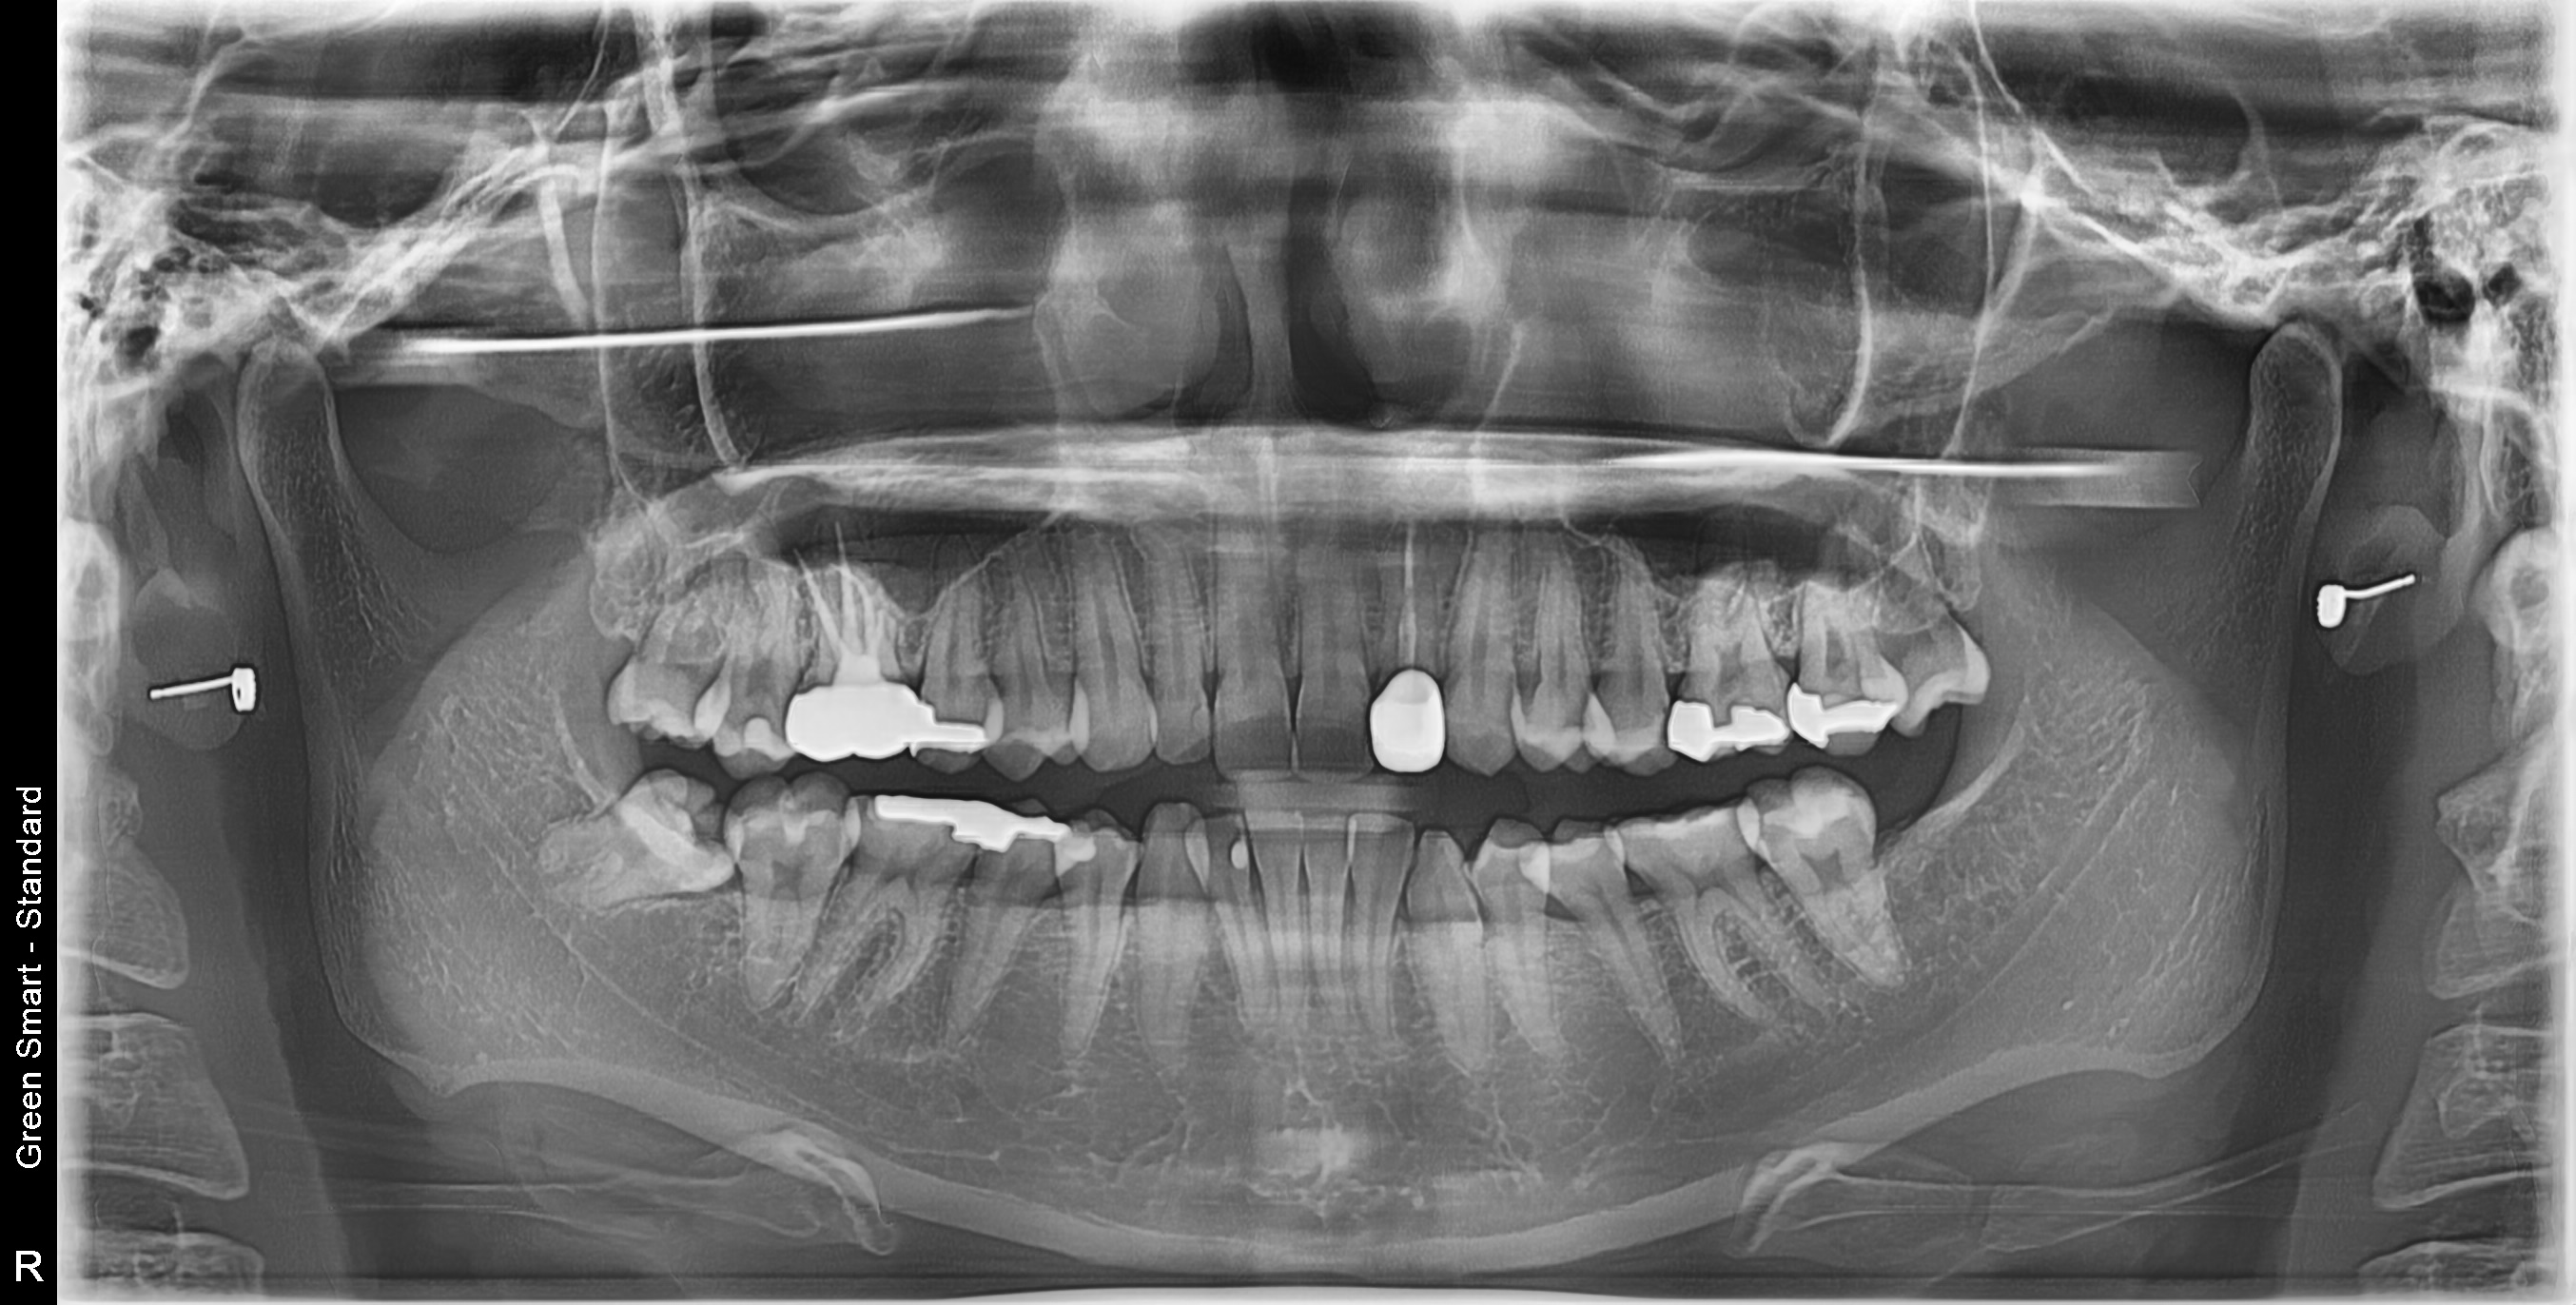

우리 병원 사랑니 발치의 특별함

2,700건 이상의 사랑니 발치 경험과 체계적인 시스템으로 차원이 다른 진료를 합니다

대학병원급 난이도 발치

일반 치과에서 "큰 병원 가보세요", "전문병원에서 빼세요" 이런 말 들어보셨나요?

복잡한 매복 사랑니 - 잇몸 속 깊이 묻혀있어도 OK

신경 근접 사랑니 - 신경 손상 걱정 없는 안전한 발치

수평 매복 사랑니 - 옆으로 누워있는 어려운 케이스도 가능

2,700건 이상의 발치 경험으로

대학병원 수준의 난이도도 안전하게 해결합니다

난이도 높은 사랑니도 뽑을 수 있나요?

네, 가능합니다. 경성 메디스 치과는 2,700건 이상의 발치 경험과 대학병원급 난이도 발치가 가능한 시스템을 갖추고 있습니다. 수평매복, 완전매복 등 일반 치과에서 큰 병원을 권유하는 어려운 케이스도 3D CT 정밀 진단으로 안전하게 발치합니다.